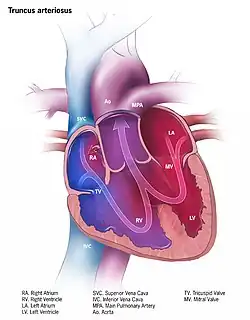

Illustration of truncus arteriosus in a fully formed heart

Illustration of truncus arteriosus in a fully formed heart

Clinical significance

Failure of the truncus arteriosus to close results in the condition known as persistent truncus arteriosus, a rare congenital heart defect. This is often just referred to as truncus arteriosus. Echocardiography is used to diagnose this condition.[4][5][6] Other pathologies of the truncus arteriosus include transposition of the great vessels (arteries in this case), and tetralogy of Fallot.[7]